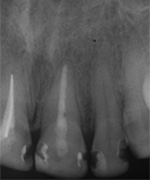

Dieser Zahn wurde schon geraume Zeit zuvor von einer Kollegin im Notdienst eröffnet und anschlies­send mit einer aufwendigen Amal­gamrestauration ästhetisch an­sprechend wieder verschlossen. (Bild 1) Uns blieb noch WK/WF, was bei massiver Überstopfung der hin­teren Wurzel auch gelang (Bild 2).

"Überstopfen ist immer noch besser als Unterstopfen" laut Koçkapan. OK, hier wurde des Guten aber ganz eindeutig zuviel getan.

Also direkt neben dem Zahn das Zahnfleisch ein wenig angehoben und zur Seite gedrängt und dann mit einem scharfen Löffel den Überschuss vollständig entfernt.

Schon 8 Monate später ist eine deutliche Verbesserung der Gesamt­situation unverkennbar (Bild 3). Verlorengegangene Knochensubstanz wurde in Teilen schon wieder aufge­baut, doch ist noch gar nichts entschieden. Schaun mer also ma'.